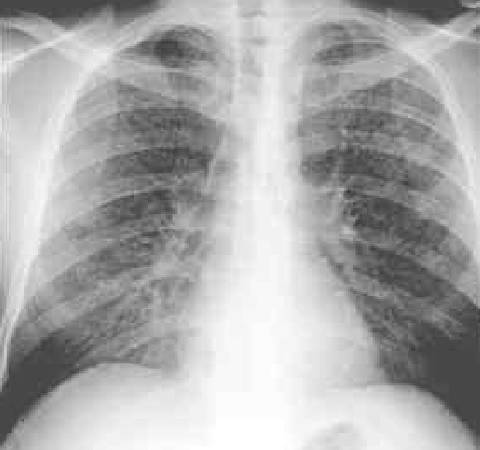

1981年,在同性恋群体中发现5例卡氏肺囊虫肺炎,病例报备美国的疾病控制中心。